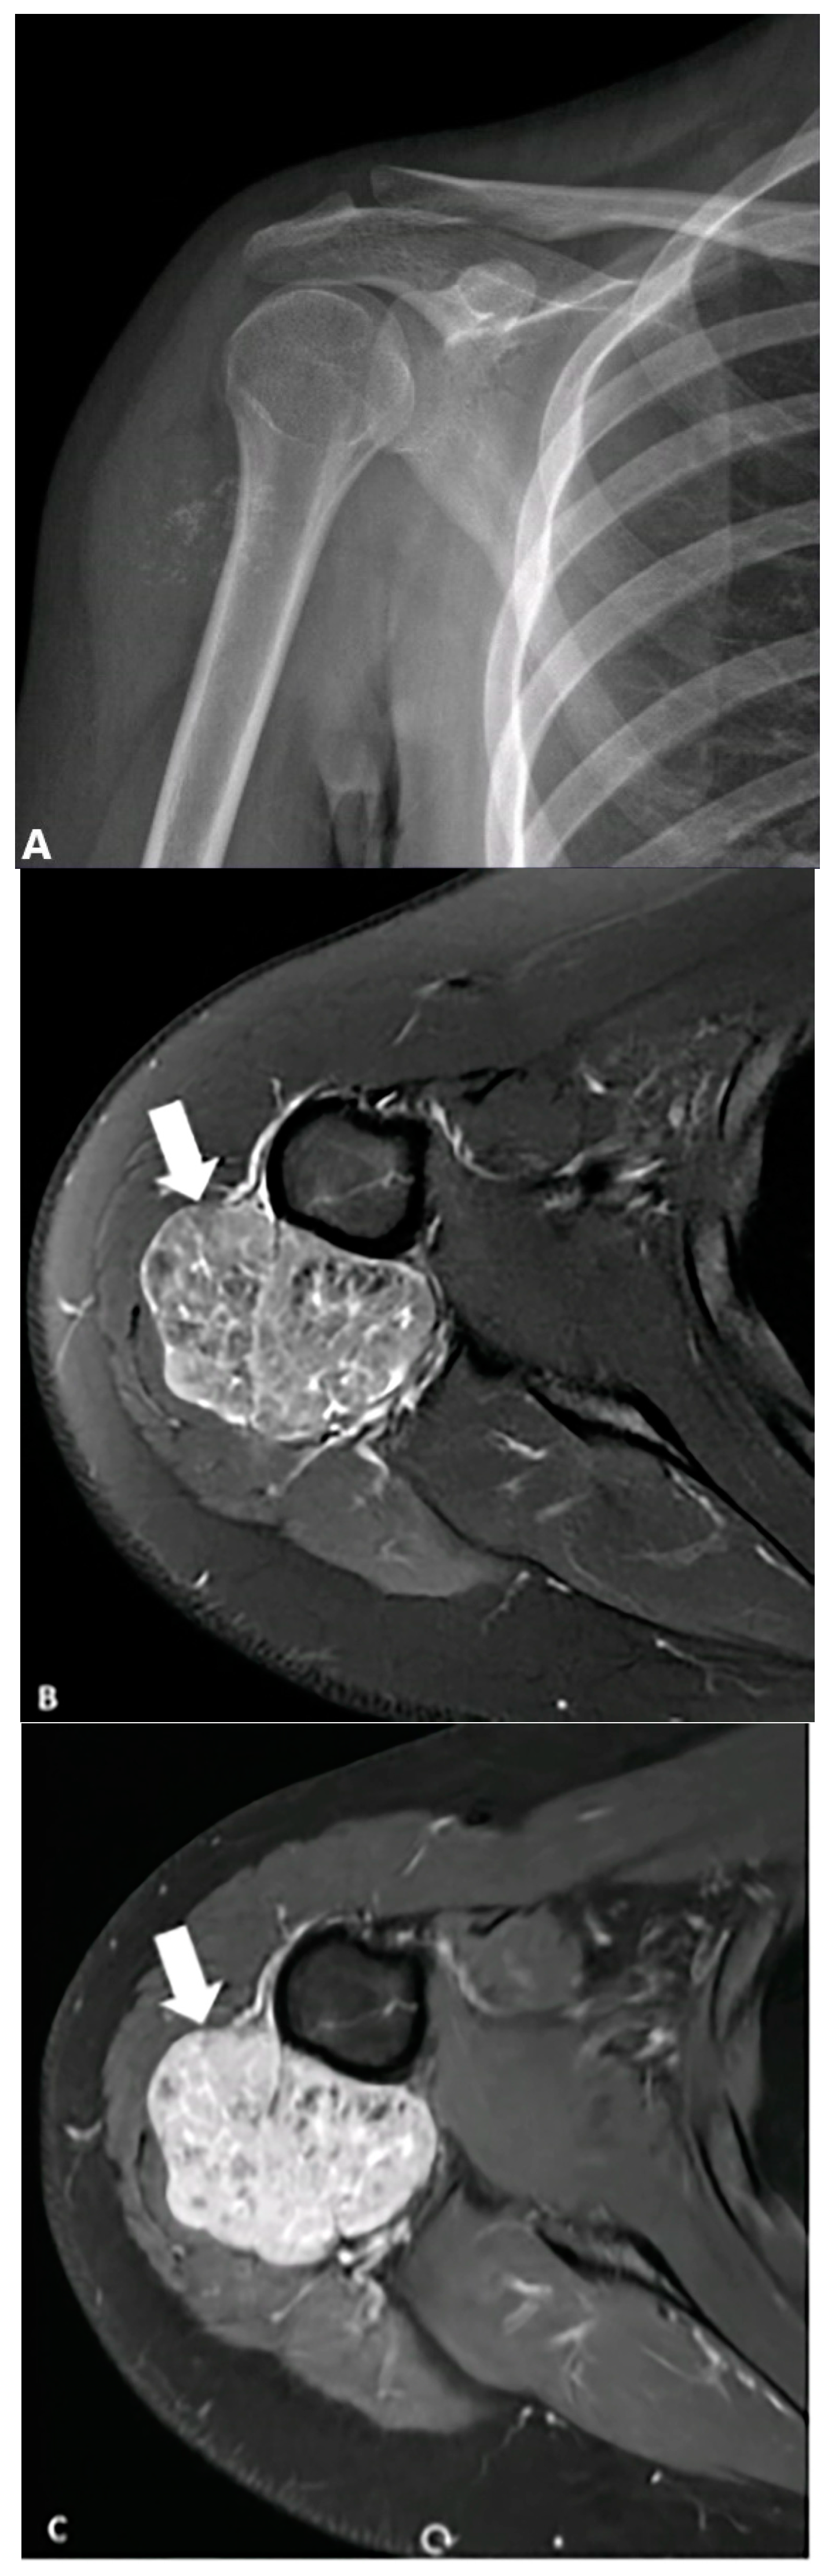

4.7. Peripheral Nerve Sheath Tumors

- Kakkar, C.; Shetty, C.M.; Koteshwara, P.; Bajpai, S. Telltale signs of peripheral neurogenic tumors on magnetic resonance imaging. Indian J. Radiol. Imaging 2015, 25, 453–458. [Google Scholar] [CrossRef]

- Isobe, K.; Shimizu, T.; Akahane, T.; Kato, H. Imaging of ancient schwannoma. Am. J. Roentgenol. 2004, 183, 331–336. [Google Scholar] [CrossRef]

- Schultz, E.; Sapan, M.R.; McHeffey-Atkinson, B.; Naidich, J.B.; Arlen, M. Case report 872. “Ancient” schwannoma (degenerated neurilemoma). Skelet. Radiol. 1994, 23, 593–595. [Google Scholar]

- Lee, S.K.; Kim, J.-Y.; Lee, Y.-S.; Jeong, H.S. Intramuscular peripheral nerve sheath tumors: Schwannoma, ancient schwannoma, and neurofibroma. Skelet. Radiol. 2020, 49, 967–975. [Google Scholar] [CrossRef]